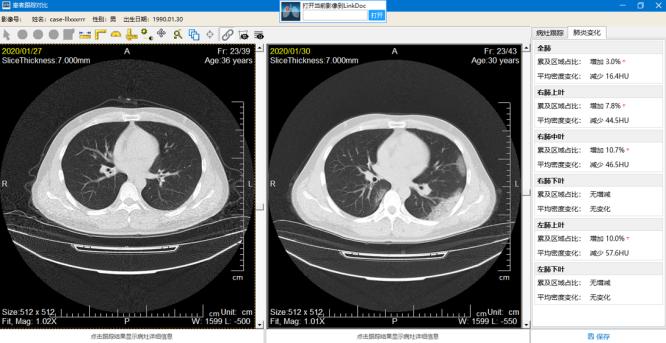

“从肺炎病变识别,到肺炎病变分析(累及区域面积、实变占比等),再到病情进展评估等,新冠肺炎AI辅诊系统都可以辅助医生。能够帮助临床专家快速定位病灶,更准确地帮助专家确定病情进展,并根据检测及分析结果生成辅助报告。”谢颖夫表示,尤其对于一些危重症患者的评估、治疗,年轻医生会感觉十分棘手,而“新冠肺炎AI辅诊系统”就有了更大的施展空间。

据悉,该系统可以通过对异常病例的分析学习,建立人工智能风险预测模型,对风险较高的患者进行预警提示,为重危患者更及时地提供有效的医疗服务。在治疗方案的推进过程中,人工智能技术可以自动追踪对比患者多次的CT,自动分析患者的病情进展情况。